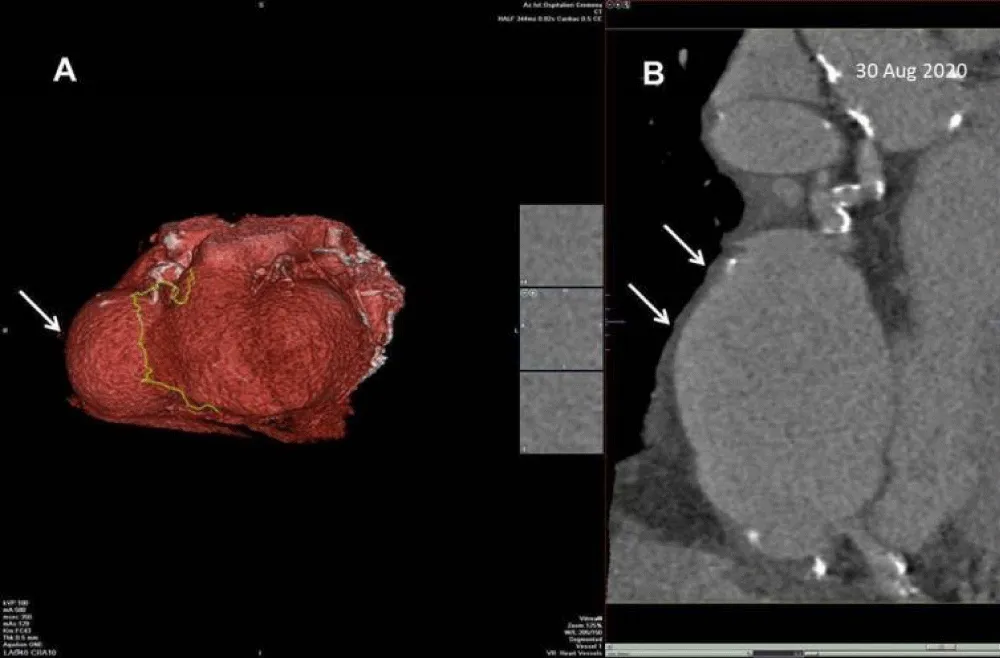

According to these echocardiographic findings, we supposed a giant coronary aneurysm. To confirm our suspicion the patient underwent Coronary Computed Tomography Angiography (CCTA) with 3D reconstruction that showed a giant aneurysm of the right coronary artery at mid-level, preceded by a mild aneurysm of the proximal tract (Figure 4a,4b). CCTA showed also two small aneurysms of the circumflex artery and diffuse atherosclerosis diseases with significant stenosis on the mid-left anterior descending artery (LAD). It was also reported significant calcification of coronary arteries (Calcium score = 3837 Agatston).

Figure 4: (a) Coronary Computed Tomography Angiography (CCTA) with 3D reconstruction. (b) CCTA with multiplanar reconstruction. Both show a giant aneurysm of the right coronary artery at mid-level (white arrow).

The coronary angiography finally confirmed the presence of the giant aneurysm in a mild tract of the right coronary artery preceded by a small one in the proximal tract, without clear evidence of contrast due to the very limited flow inside the lesion. It also showed the presence of two small aneurysms of the circumflex artery and a critical stenosis of mid tract of LAD.